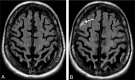

Background and purpose: AD is one of the few leading causes of death without a disease-modifying drug; however, hopeful agents are in various phases of development. MR imaging abnormalities, collectively referred to as amyloid-related imaging abnormalities, have been reported for several agents that target cerebral Aβ burden. ARIA includes ARIA-E, parenchymal or sulcal hyperintensities on FLAIR indicative of parenchymal edema or sulcal effusions, and ARIA-H, hypointense regions on gradient recalled-echo/T2* indicative of hemosiderin deposition. This report describes imaging characteristics of ARIA-E and ARIA-H identified during studies of bapineuzumab, a humanized monoclonal antibody against Aβ.

Results: Thirty-six patients were identified with incident ARIA-E (17.1%, 36/210) and 26 with incident ARIA-H (12.4%, 26/210); of those with incident ARIA-H, 24 had incident microhemorrhages and 2 had incident large superficial hemosiderin deposits.

Conclusions: In 49% of cases of ARIA-E, there was the associated appearance of ARIA-H. In treated patients without ARIA-E, the risk for incident blood products was 4%. This association between ARIA-E and ARIA-H may suggest a common pathophysiologic mechanism. Familiarity with ARIA should permit radiologists and clinicians to recognize and communicate ARIA findings more reliably for optimal patient management.